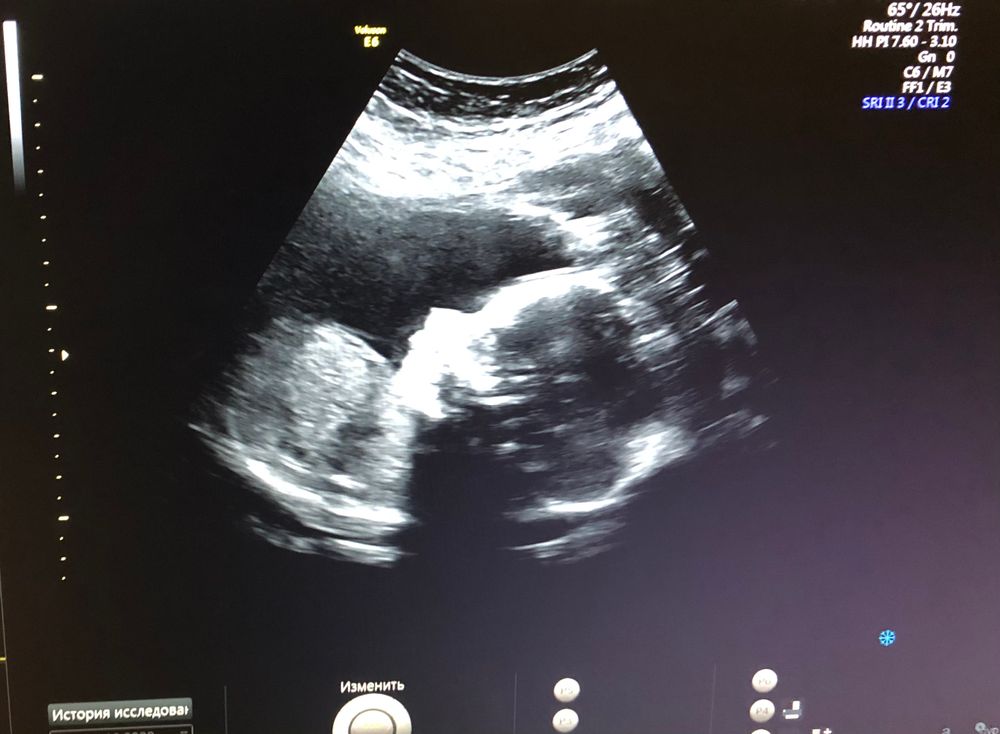

2 скрининг ✅

Всем приветик. Сегодня я прошла 2 скрининг, и у нас ..... Девочка 👧🏻 🎀

По заключение скрининга патологий нет. Это самое главное 🙏🏻